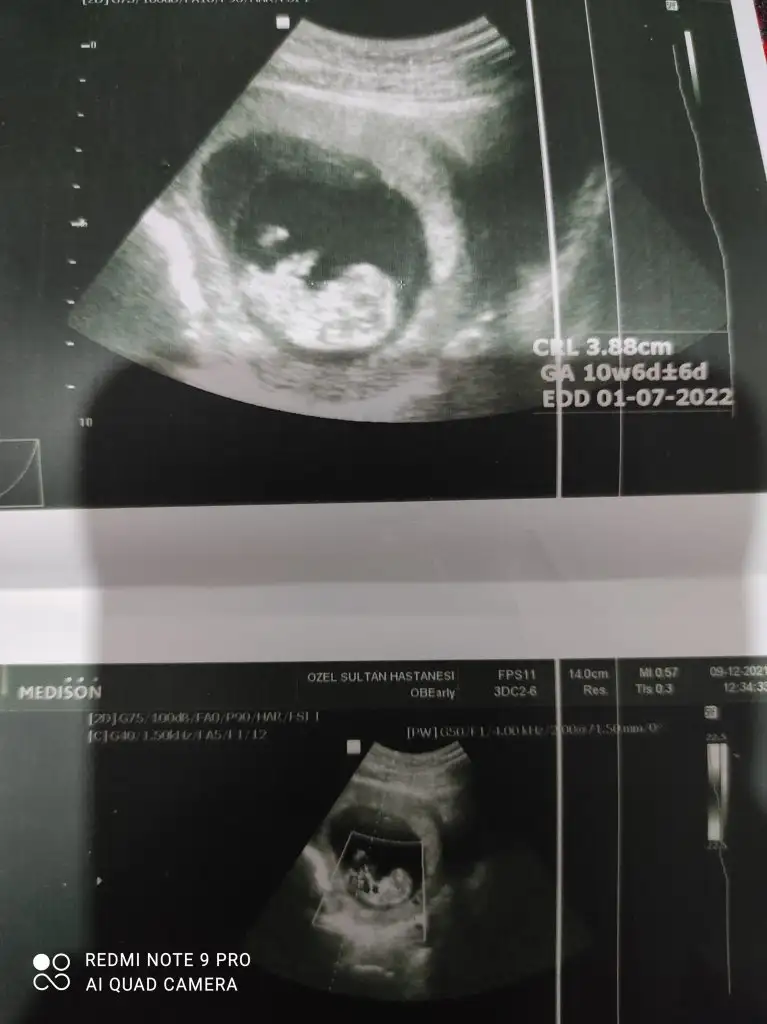

dr soylemeden siz gorun genital nub teorisi ( bebegin cinsiyeti)

10+0 çıktı. Ikra meyra Ikra meyra ve diğer arkadaşlar umarım bellidir😁

Erkek ve kız için 11 + 12+ yada 13 hafta usg görüntüsü olmalı açıklamalar asagıda yazıyor 😊 rabbim herkesin gönlüne göre nasip etsin inşallah .. ecmain

[/B]Eki Görüntüle 473828 gordugunuz gibi ust taraftaki simgedende anlasildigi gibi eger cikinti paralel ise kiz

yok 30°lik bir aciyla yukari dogru bakiyorsa %99 oglunuz olacak demektir simdi bi kac ornek resimler daha koyacagim kiziminkide dahil